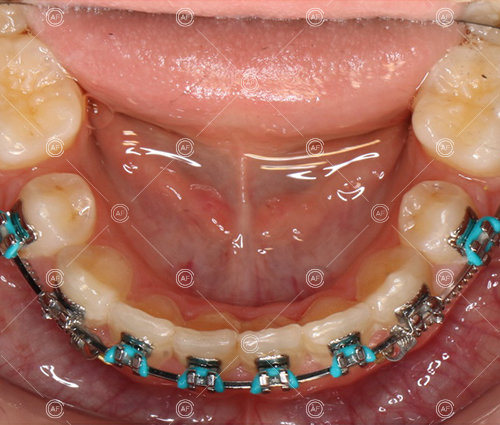

- Extraction of upper right 5, upper left 4, lower left 5, lower right 5

- Fixed appliances in the upper and lower arches

Treatment progressed by starting with thin, flexible nickel titanium archwires of a round diameter, transitioning to a rectangular nickel titanium archwire before eventually working up to a working archwire (1925 stainless steel).

Residual space from the extractions were closed using upper and lower nickel titanium closing coils. Class 2 elastics were used to facilitate space closure in order to gain class 1 buccal segments.